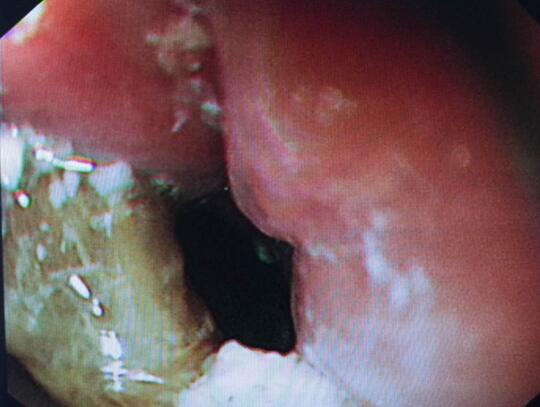

内镜中心王莹副主任考虑到患者病情复杂且高龄,不具备急诊外科手术条件,在确保患者安全情况下行内镜下异物钳取术、钛夹封闭损伤治疗。术中观察到梭形枣核嵌顿于患者食管上端,一侧食管壁可见纵形全层伤口,损伤非常严重。王主任克服困难,以她熟练的操作最终将异物顺利取出。

异物